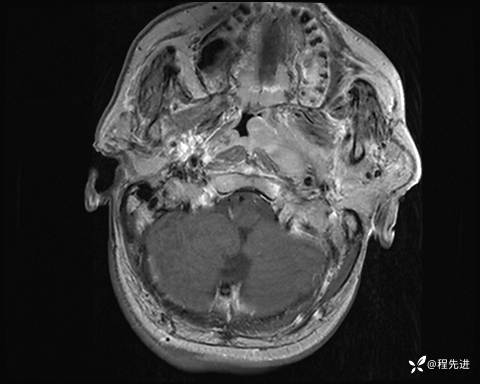

MRI平扫+增强:

T1增强: